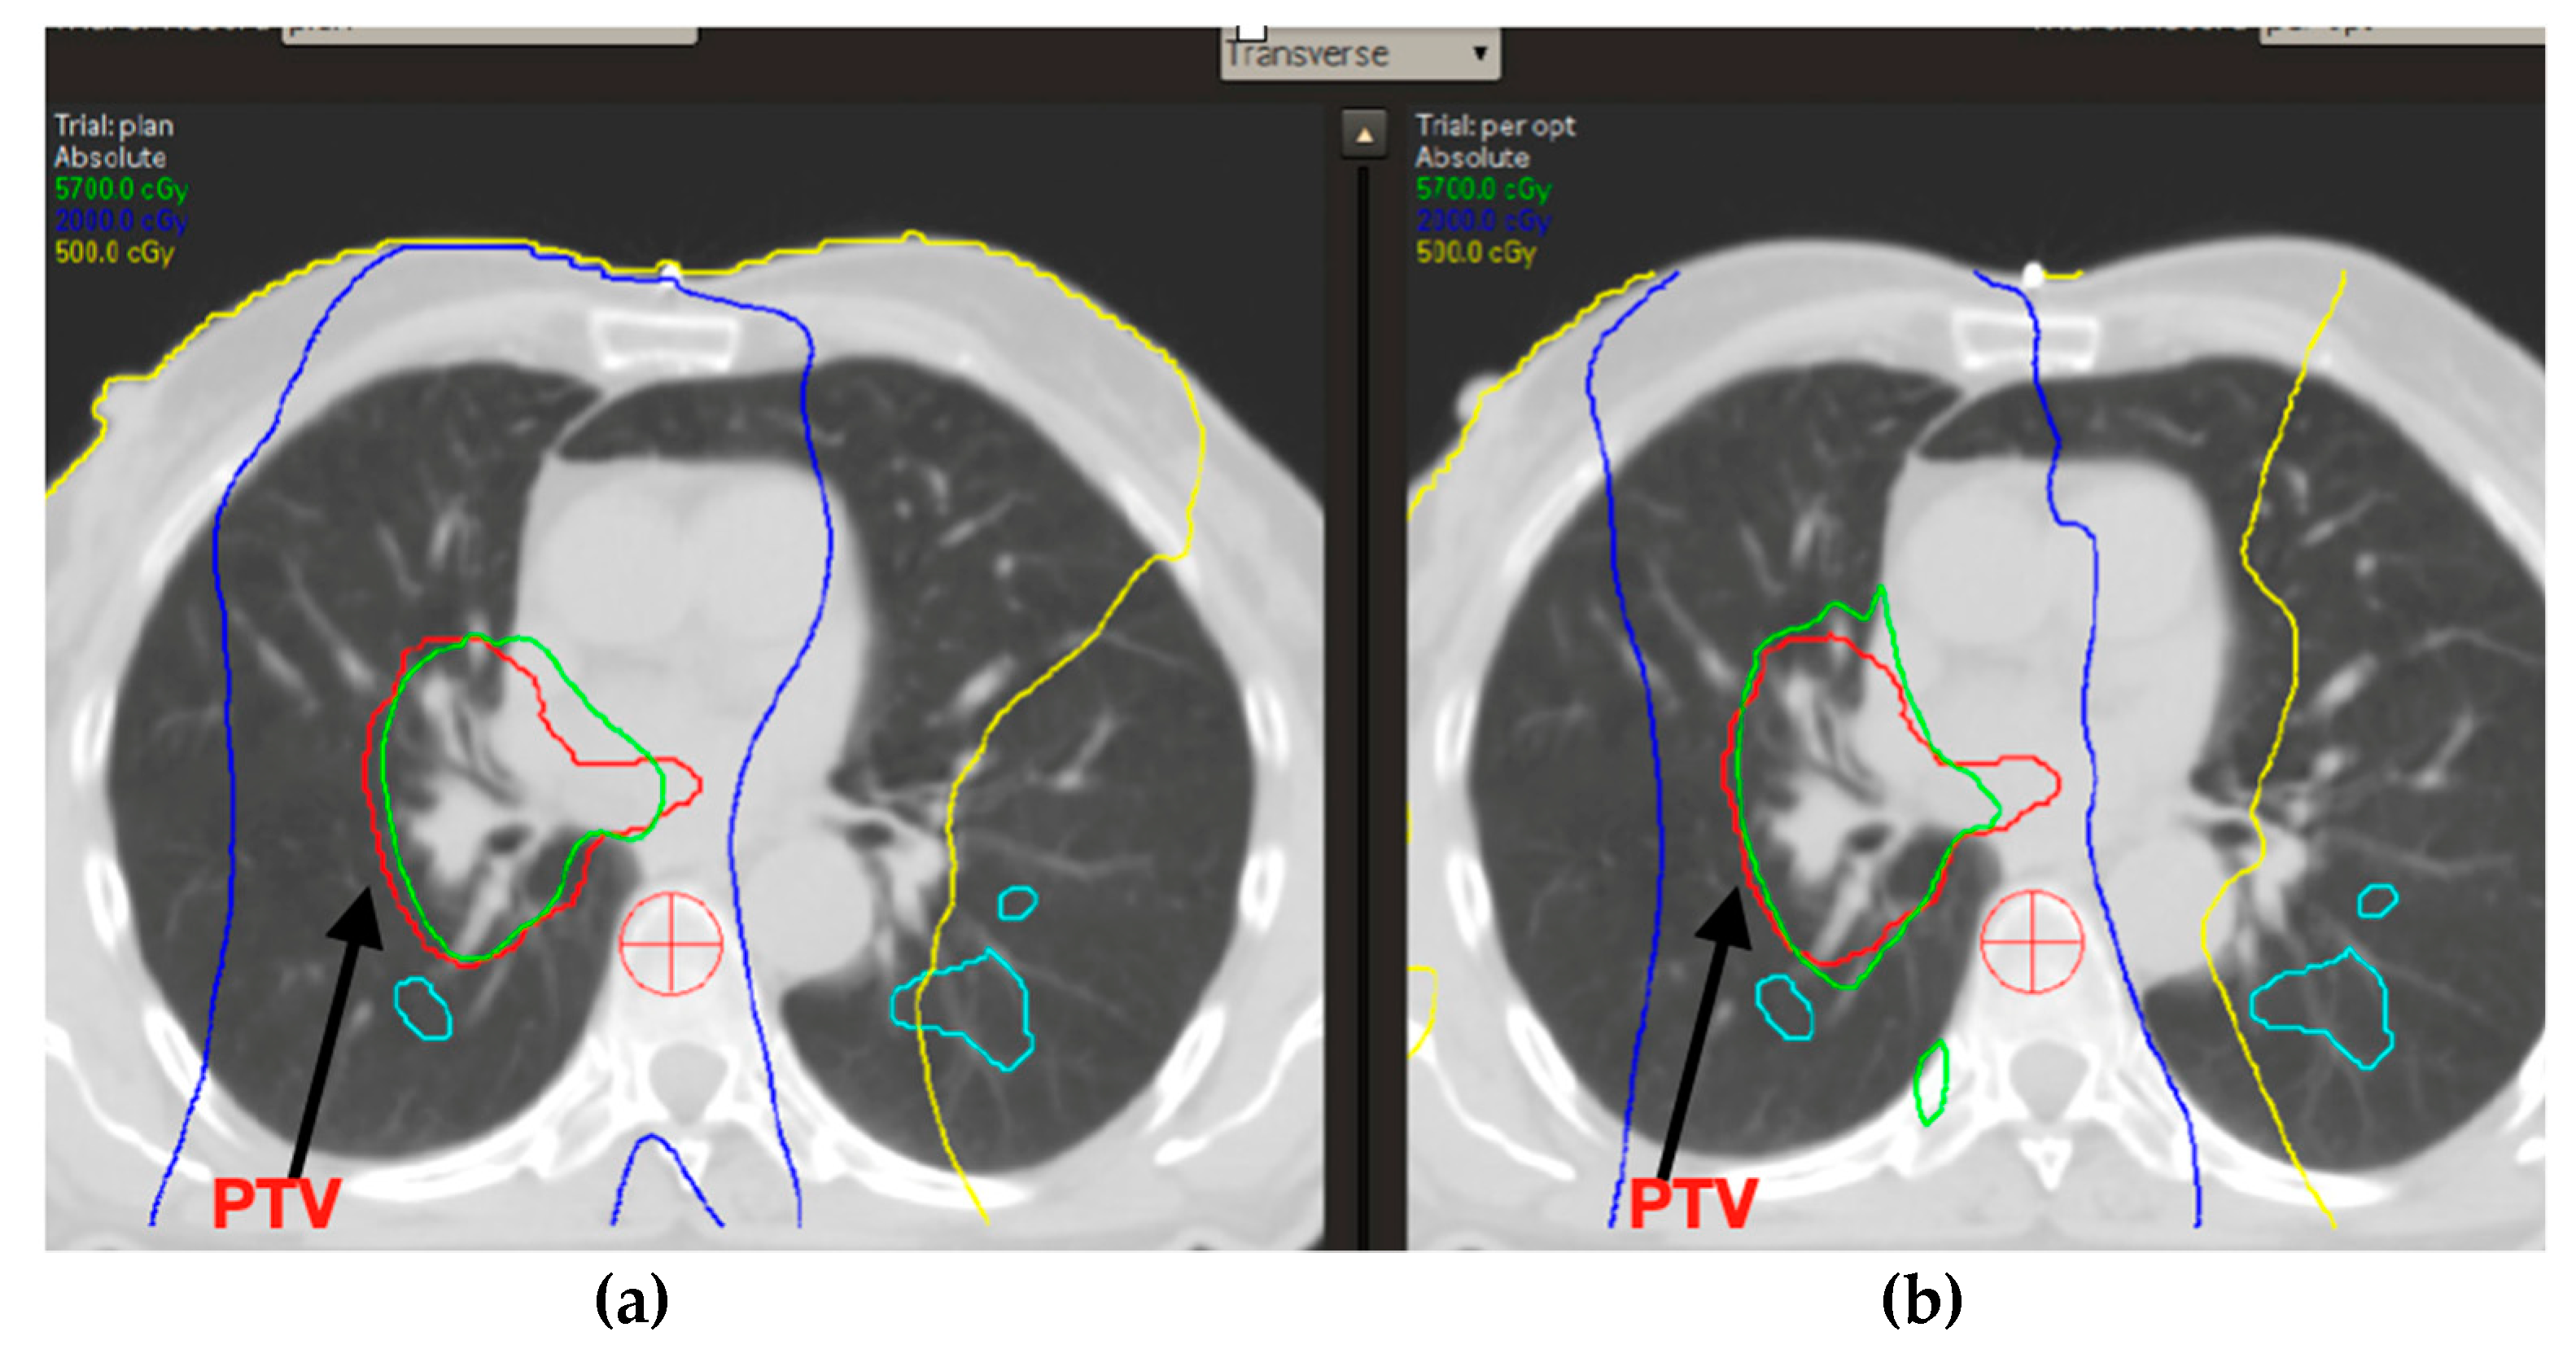

In addition, over the standard plan obtained for treatment, an in silico one was calculated for each patient introducing lung perfusion provided by SPECT CT scan. For this second treatment plan obtained after the SPECT optimization, deformable co-registration between CT simulation images and the SPECT/CT ones was performed using the VelocityTM software 4.0 (Varian Medical Systems, Crawley, UK). First performed a fusion between the simulation CT and the PET CT. Then, we automatically fused them with the corresponding PET perfusion images (Figure 1). The planning system used was Pinnacle. From the literature, the best perfused lung areas could be considered those with a perfusion range ranging from 20% of maximum perfusion to 80% of maximum perfusion [15].

Since the exploratory nature of this study, the regions of interest representing lung volumes with a perfusion of at least 20% 40%, 60% and 80% of the maximum perfusion value were created on the treatment plan (xx%IsoROI) (Figure 2).

Figure 1. Deformable co-registration between CT simulation images and the SPECT/CT.

Figure 3. (a) Standard RT plan and (b) SPECT/CT-optimized RT plan.